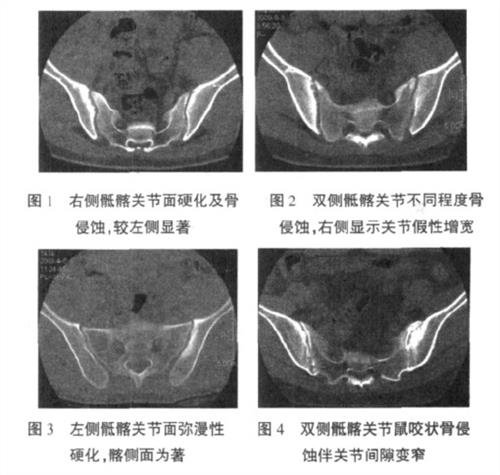

ca69c7189f9857e58a54068013965fe9.jpg

(圖:骶髂關(guān)節(jié)具體位置如圖所示)

b7192e3cbf49b5587a313c8b1dcf063e.jpg

(圖:骶髂關(guān)節(jié)構(gòu)架示意圖)

52ce5f0fe81166b3cba68dc2ba01e777.jpg

骶髂關(guān)節(jié)炎與強(qiáng)直性脊柱炎的區(qū)別

骶髂關(guān)節(jié)炎多涉及關(guān)節(jié)軟骨、髖部肌肉等。骶髂關(guān)節(jié)炎的主要癥狀就是疼痛,且為隱匿發(fā)作、持續(xù)鈍痛,但一般短暫休息后可以得到一定緩解。臨床表現(xiàn)的疼痛,如:下腰痛、臀區(qū)疼痛、大腿近端疼痛及腹股溝區(qū)疼痛等;另有一個(gè)比較明顯的病癥就是晨僵——晨僵多是因滑膜炎的存在,但和類風(fēng)濕性關(guān)節(jié)炎不同,晨僵持續(xù)時(shí)間比較短暫,一般不超過(guò)30分鐘,且在活動(dòng)后即可逐漸緩解。

強(qiáng)直性脊柱炎會(huì)累及多個(gè)關(guān)節(jié),主要會(huì)累及骶髂關(guān)節(jié)、髖關(guān)節(jié)、脊柱,為雙側(cè)性;手足小關(guān)節(jié)、膝、踝等也可被累及。患者開(kāi)始發(fā)病時(shí),會(huì)表現(xiàn)為多有全身無(wú)力、食欲不振、貧血、低熱、心悸、出汗等。而發(fā)病累及的范圍也會(huì)逐漸發(fā)生變化:病變初期常累及骶髂關(guān)節(jié),表現(xiàn)為下腰痛、彎腰受限、晨起腰部僵硬等;隨病癥加深,疼痛逐步加劇,病變范圍亦逐漸由腰骶部向上往胸、頸段脊柱發(fā)展,導(dǎo)致脊柱活動(dòng)困難,使病患后發(fā)展為畸形駝背。強(qiáng)直性脊柱炎骶髂關(guān)節(jié)疼痛特點(diǎn)是休息不能緩解,活動(dòng)后方能緩解,這也是與腰椎間盤突出、腰椎管狹窄、腰部外傷的區(qū)別點(diǎn)。強(qiáng)直性脊柱炎輕癥者,僅會(huì)感覺(jué)骶髂關(guān)節(jié)部僵硬、肌肉酸痛。

2、骶髂關(guān)節(jié)炎疼痛感強(qiáng)烈:時(shí)常伴有放射性疼痛,在立位屈曲時(shí)產(chǎn)生嚴(yán)重腰痛,或造成一側(cè)骶髂關(guān)節(jié)向前或向后的半脫位,所以骶髂關(guān)節(jié)炎的癥狀臨床有跛行足及足后根痛;骶髂關(guān)節(jié)炎在進(jìn)行關(guān)節(jié)后防穿刺時(shí)有膿液流出,X線早期無(wú)明顯改變,晚期關(guān)節(jié)面硬化顯示蟲蝕樣改變,關(guān)節(jié)面增厚,有時(shí)有死骨;患病的關(guān)節(jié)出現(xiàn)紅、腫、熱、痛的癥狀。